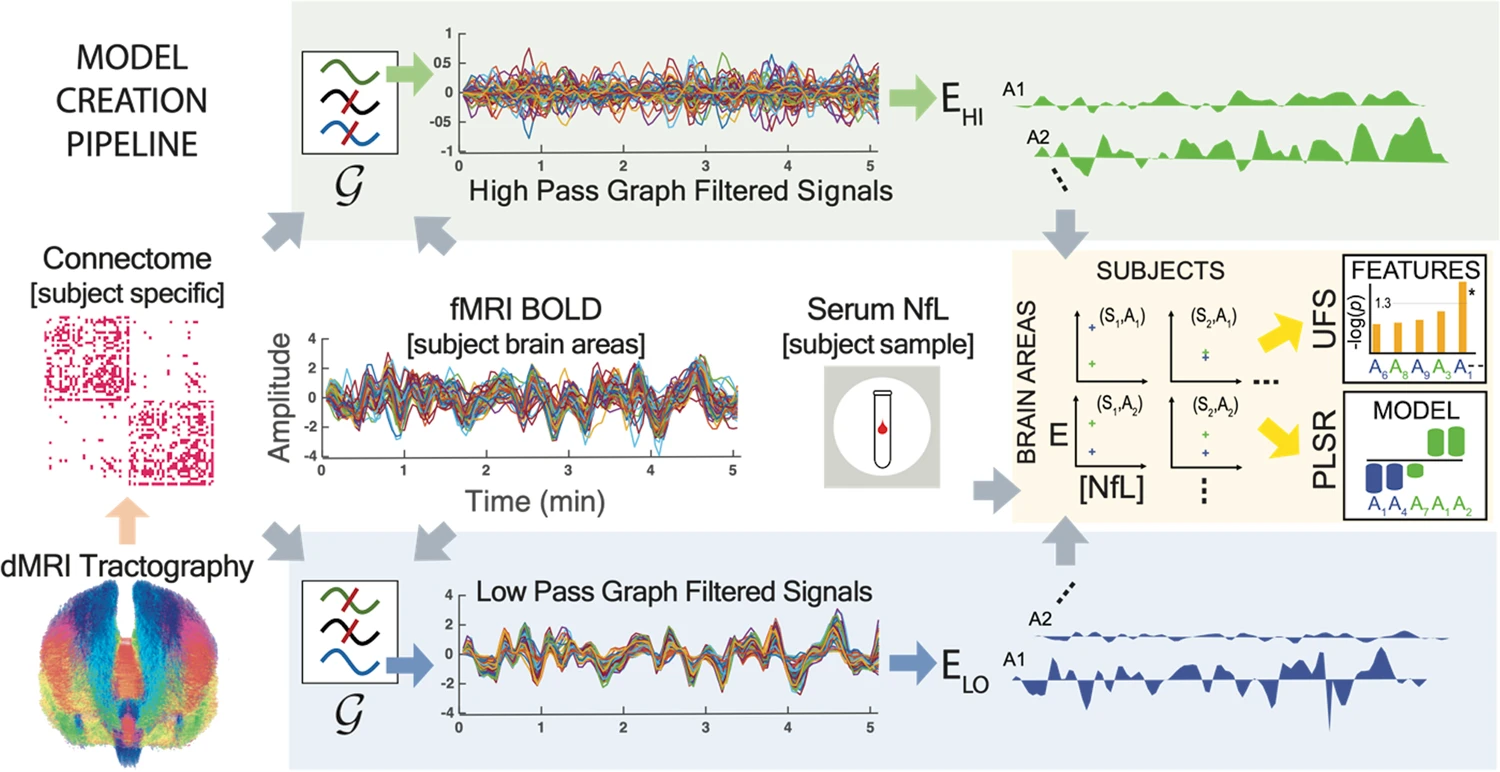

Data engineering, analysis of multimodal dataset, and multiscale modeling of neurostimulation in obsessive-compulsive disorders.

- Design and implementation of an interface between brain modeling and machine learning algorithms in Python and C++.

- Parameter optimization using evolutionary algorithms. Integration of libraries into service architecture for cloud computing.